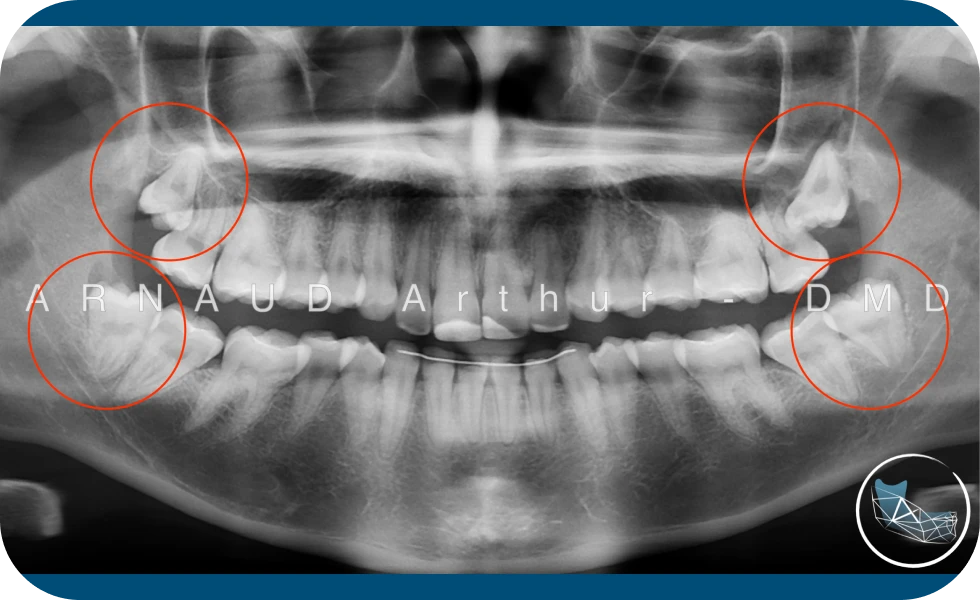

Les dents de sagesse, aussi appelées troisièmes molaires, sont les dernières dents à se développer. Alors que certaines dents de sagesse poussent normalement, la plupart des bouches sont trop petites pour accueillir un troisième ensemble de molaires. Il est important de réaliser des examens dentaires réguliers et de détecter tôt les dents de sagesse afin de savoir si elles pourront se développer sans causer de problèmes.

Dans la plupart des cas, il est recommandé de faire retirer les dents de sagesse avant que les dents ne soient complètement formées au niveau des racines. Les suites opératoires seront meilleures et les risques de complications qui peuvent survenir seront réduits.

Au fur et à mesure que les dents de sagesse se développent, les racines deviennent plus longues et l’os de la mâchoire plus dense.

Le moment idéal est chez certains patients, autour de 12 ou 13 ans et pour d’autres, ce ne sera peut-être qu’au début de la vingtaine.

- Des maladies non infectieuses peuvent également survenir en association avec une dent de sagesse incluse. Les kystes sont des cavités remplies de liquide/tissu à l’intérieur de l’os de la mâchoire qui se développent à la suite de dents incluses et grandissent lentement, sans douleur en détruisant l’os de la mâchoire et parfois les dents. Ils peuvent être très difficiles à traiter si vos dents de sagesse ne sont pas retirées à l’adolescence.

- Les dents de sagesse incluses peuvent contribuer à l’encombrement de vos dents. Ceci est plus visible avec les dents de devant à la mâchoire du bas et est le plus souvent observé après qu’un patient ait eu un appareil dentaire. Il existe un certain nombre de facteurs qui provoquent l’encombrement des dents après un appareil dentaire ou au début de l’âge adulte. Les dents de sagesse retenues et incluses peuvent être un facteur contributif.